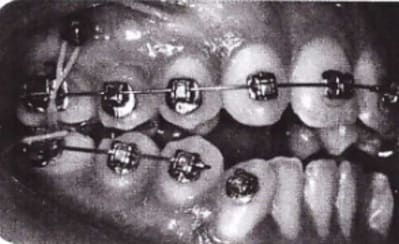

Merci jt2000, seespan et inset pour votre aide. Voici finalement le dispositif que l'on a choisi car je voulais me servir de l'implant comme ancrage.

je vous montrerai l'evolution, favorable ou.... défavorable.

je suis a l'écoute des ortho pour leurs conseils et critiques...

Si tu fais comme ça mécaniquement il n'y a pas de problème l'implant empéchant la protrusion de la 11.

Normalement il ne devrais pas y avoir de problème.

Juste faire attention a ce que la force ne soit pas trop élévé normalement il ne faut pas plus de 10g pour une intrusion.

Personnellement j'aurait utiliser deux bracket ou danchemon un sur la provisoire et un sur la 11.

Pour contrôler le mouvement de la 11 avec un fils s'a aurait était plus précis la force aurait était continue aussi.

Mais d'un autre coté il n'y a rien qui vous empéche de fignoler aprés.